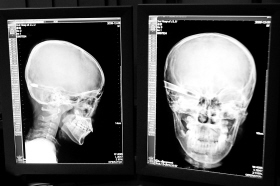

“還是先做個X光透視,看一下箭桿到底有多深。”眼科醫生緊急趕到CT室查看,和放射科的幾位醫生共同研究后,決定先讓小沖做X光透視。

“如果再用點力,就從后腦穿出來了!”由于小沖無法移動,醫生拿來移動插座,將透視的光板放在小沖的移動病床上,透視后讓在場的醫生都吃了一驚:箭桿直接穿過了大腦和小腦,箭尖兒直抵后顱骨,足足有10余厘米。